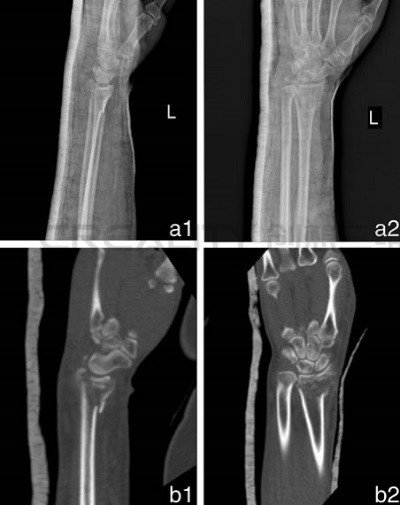

從以前跟蹤過的案例中,其中3D打印機(jī)已被用于創(chuàng)建假肢制造手臂模型以幫助修補(bǔ)骨折,甚至制作植入物來治愈損傷,但在本次研究中,研究人員評(píng)估了該技術(shù)在其中進(jìn)行改進(jìn)的能力。48名患有橈骨遠(yuǎn)端骨折的患者(最常見的上身損傷類型之一)參與了這項(xiàng)研究。

CT數(shù)據(jù)以DICOM格式存儲(chǔ),然后在3D打印機(jī)中使用PLA耗材打印之前通過Mimics軟件進(jìn)行轉(zhuǎn)換。科學(xué)家們報(bào)告了3D打印模型的成功,因?yàn)樗鼈兦宄仫@示了骨折的位置,這種手術(shù)每次大約需要兩個(gè)半小時(shí)。